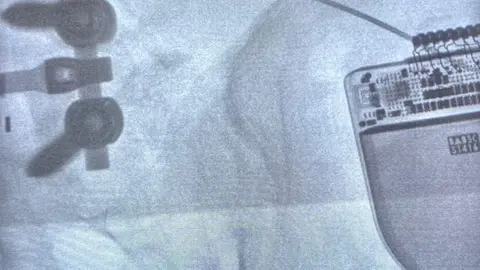

Esta intervención se llevó a cabo con la colaboración de uno de los expertos más reputados del país en el tratamiento del dolor, el doctor David Abejón